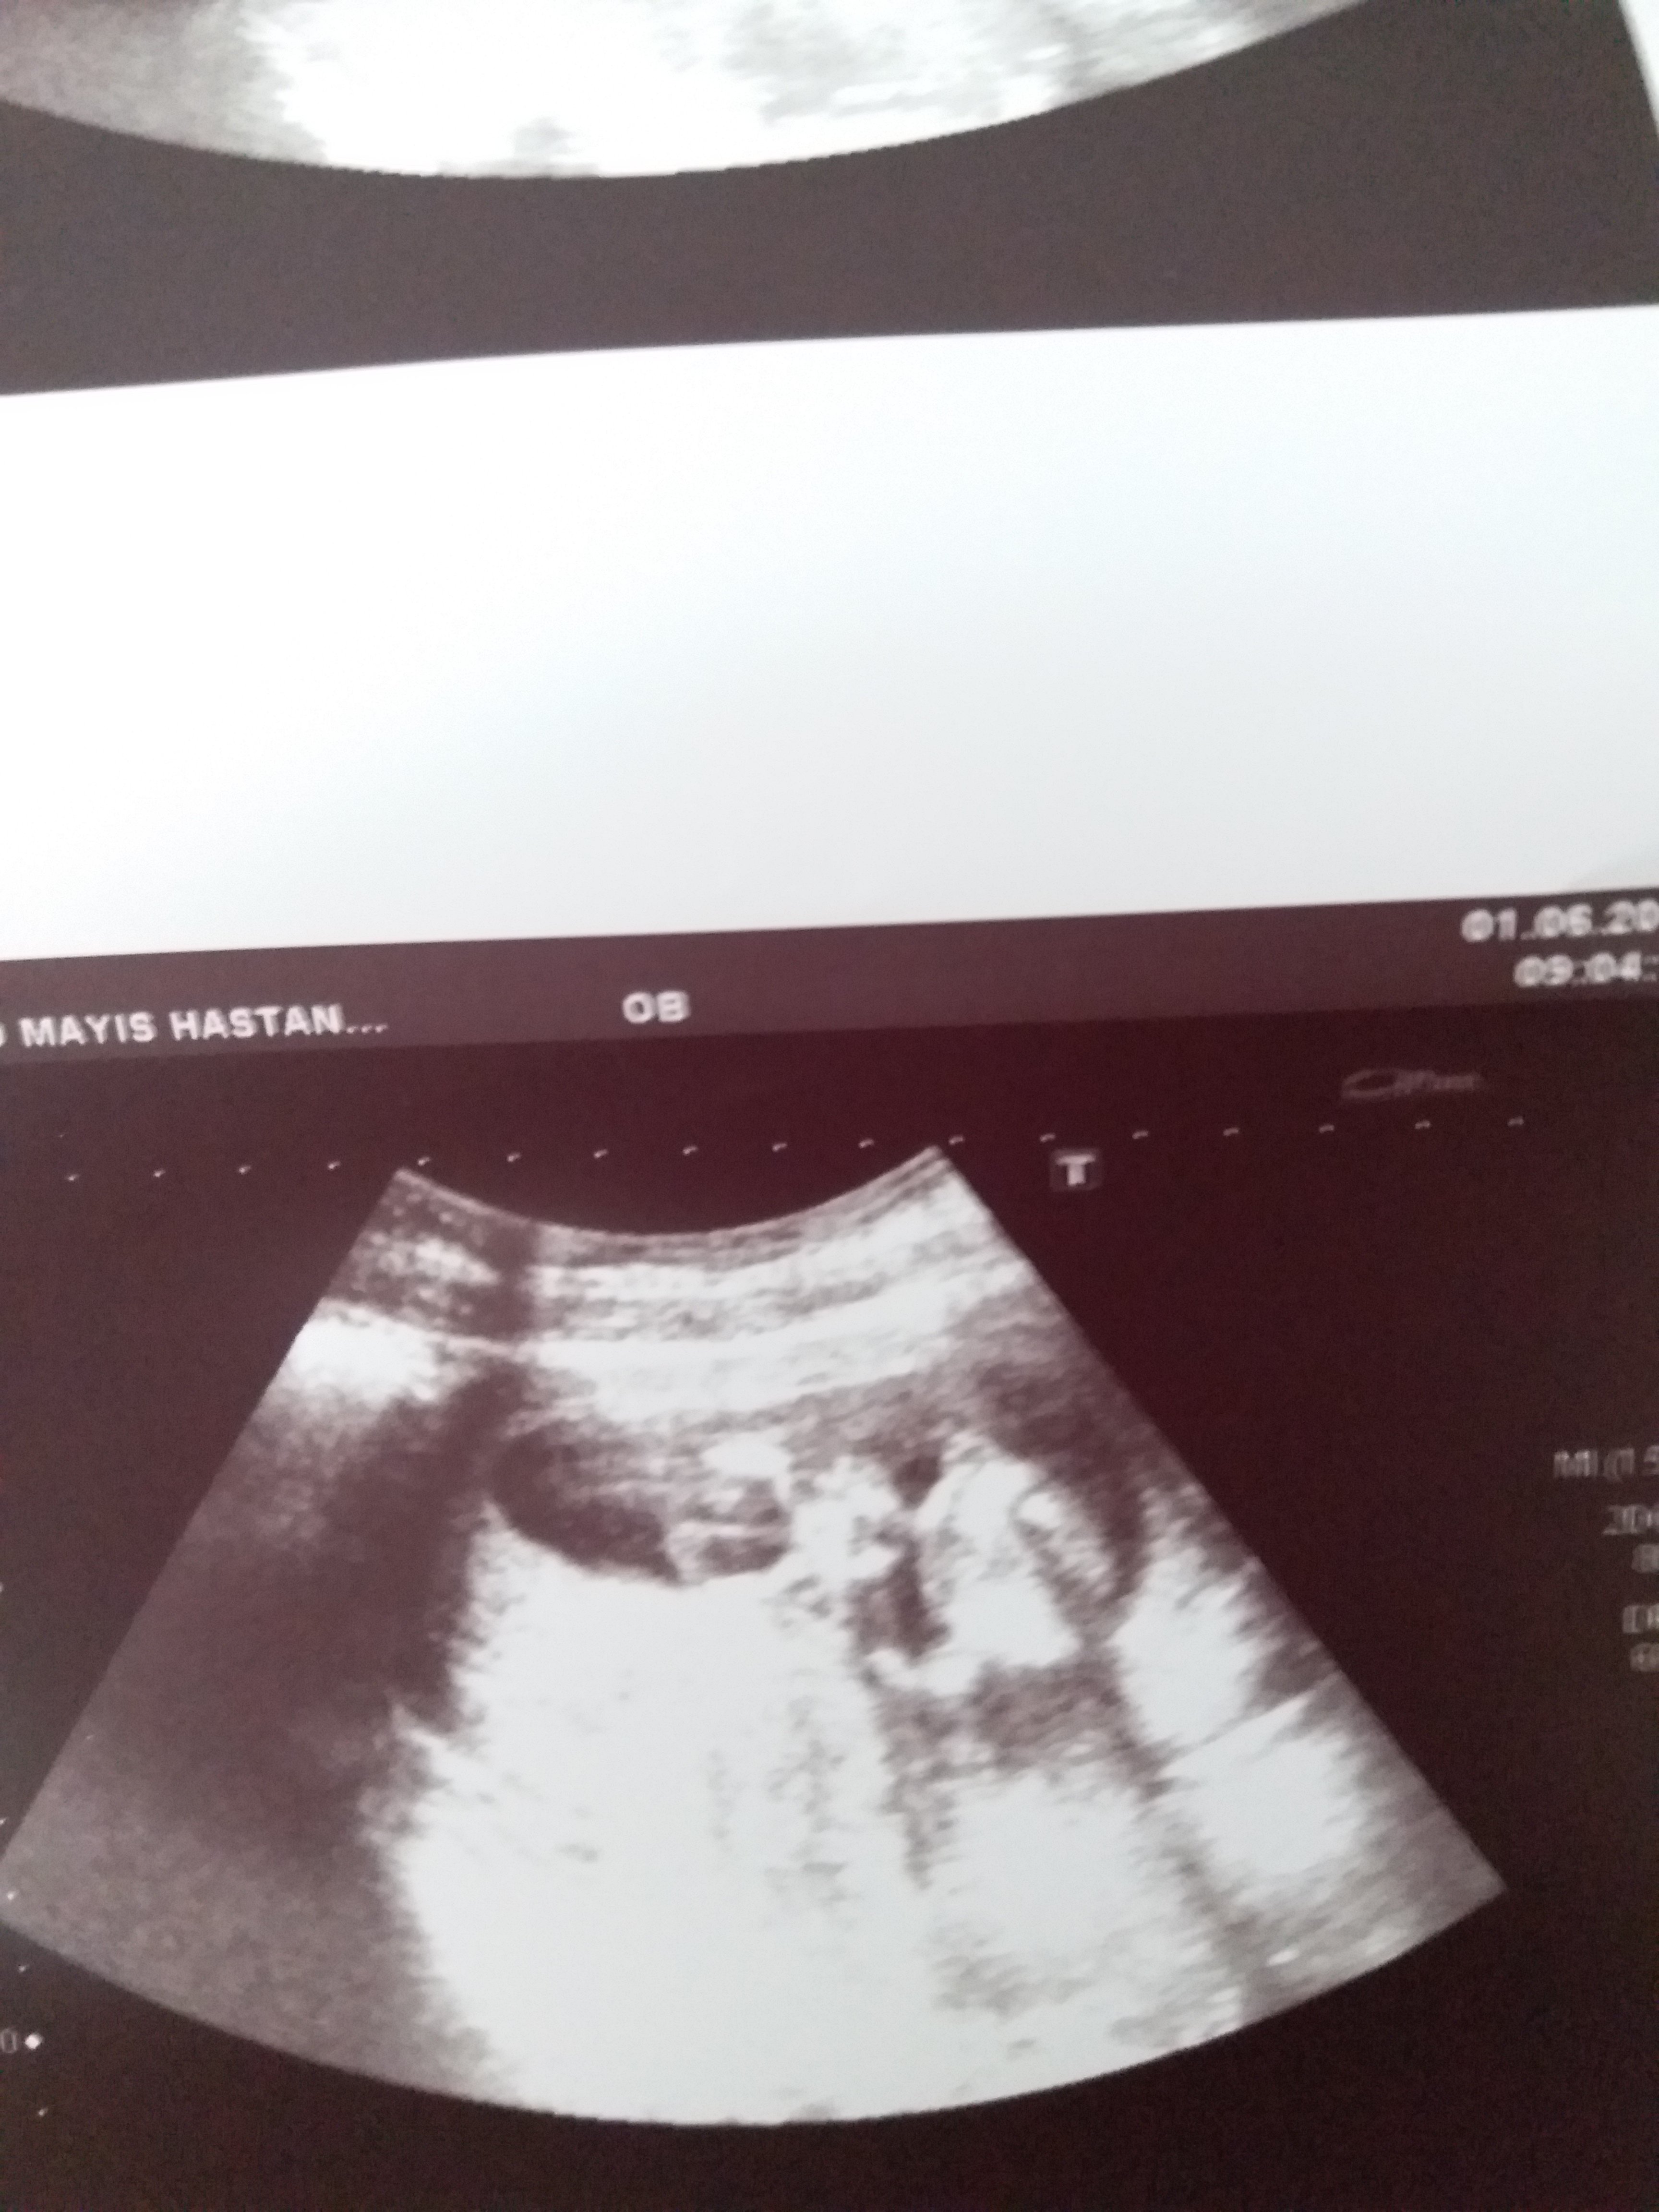

Sizce cinsiyet nedir ya bu hafta tekrar gittim doktora net konuşmadı 12 haftadayız lütfen bilen Allah rızası için yardımcı olsun

• 20190601_113851.jpg

20190601_113851.jpg

1,4 MB · Görüntüleme: 800